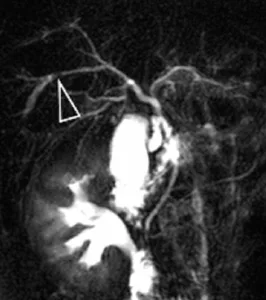

Figure 13. Intérêt du gadolinium pour l’exploration des cholangites sclérosantes primitives : l’injection de produit de contraste permet l’étude du rehaussement biliaire et l’analyse du parenchyme hépatique à la recherche d’un éventuel cholangiocarcinome. De plus, la comparaison d’acquisitions de bili IRM avant (A) et après (B) injection de gadolinium montre que cette injection peut réduire le « bruit de fond » lié aux structures vasculaires. L’analyse des voies biliaires est ainsi facilitée. Ici, on note un aspect typique de CSP